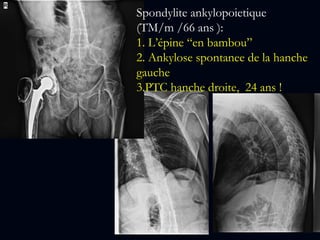

Spondylite ankylopoietique

(TM/m /66 ans ):

1. L’épine “en bambou”

2. Ankylose spontanee de la hanche

gauche

3.PTC hanche droite, 24 ans !